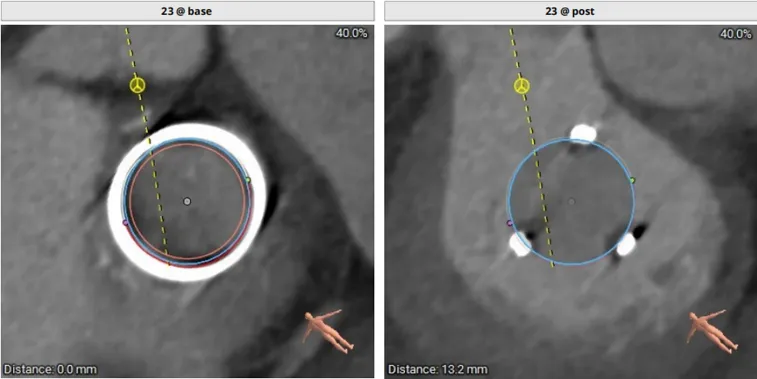

模拟植入26mm的S3瓣膜,评估LVOT阻塞风险:

3.最小Neo-LVOT面积= 260.4mm2>180mm2

综合评估后LVOT梗阻风险低。